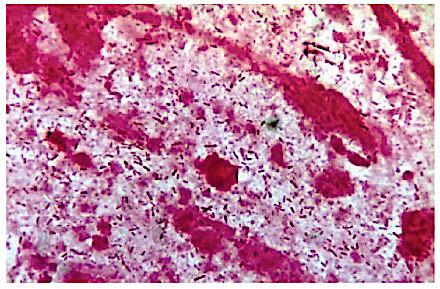

Pseudomonas aeruginosa er en aerob gramnegativ bakterie tilhørende familien Pseudomonadaceae. Den er i stand til at leve under helt eller delvis iltfrie forhold blandt andet via nitratomdannelse. Denne egenskab er essentiel for P. aeruginosa i forbindelse med lungeinfektioner hos patienter med cystisk fibrose (CF), hvor tykke lag af biofilm begrænser diffusionen af ilt.